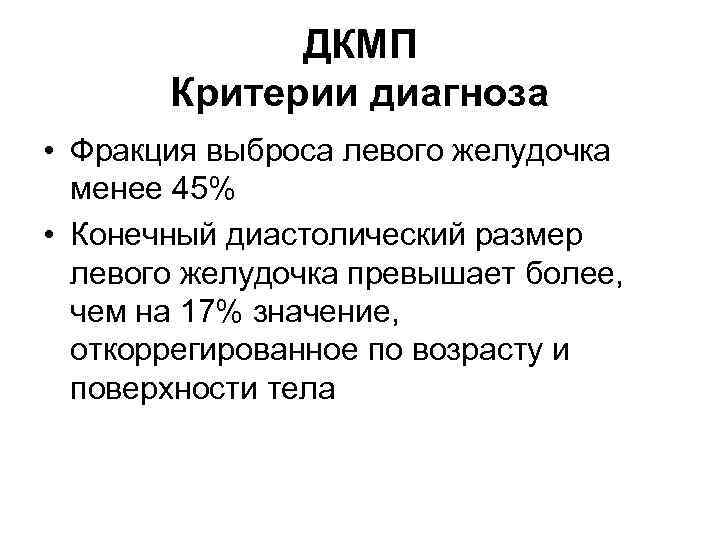

ДКМП Критерии диагноза • Фракция выброса левого желудочка менее 45% • Конечный диастолический размер левого желудочка превышает более, чем на 17% значение, откоррегированное по возрасту и поверхности тела

ДКМП Критерии диагноза • Фракция выброса левого желудочка менее 45% • Конечный диастолический размер левого желудочка превышает более, чем на 17% значение, откоррегированное по возрасту и поверхности тела